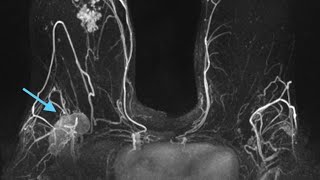

Общая выживаемость пациентов с метастазами в головной мозг после радиохирургического лечения

Выживаемость пациентов с метастазами в головной мозг после радиохирургического лечения. Дискутант